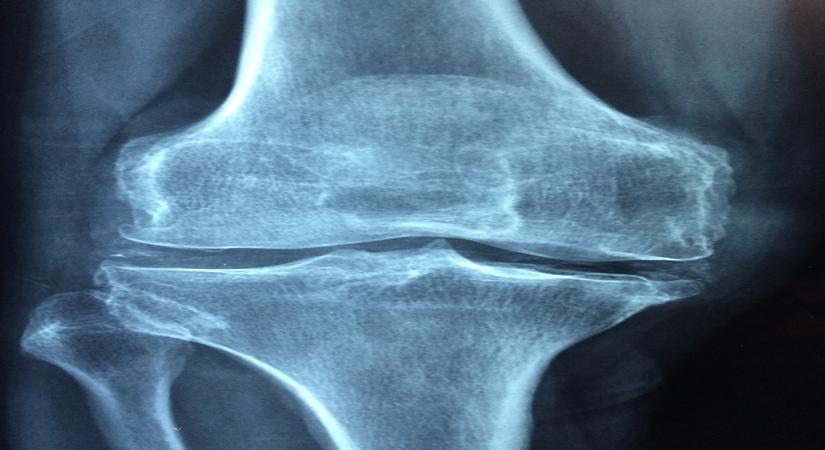

March 11, 2020 (IANSlifeOsteoporosis is one of the leading causes of fractures in post-menopausal women and elderly people.

When we are active in any form, even simple jogging, bones will absorb extra minerals and provide the necessary strength our body needs. While, the lack of enough exercises will lead to continuous resorption and continuous shedding of minerals which ultimately leads to thinner, fragile and bones which are more likely to break due to increased holes and porosity.

Although different exercise routines are always trending to increase bone mass density like weight bearing, resistance, stretching and flexibility, but recent studies show that even a “brief duration” of high intensity, high impact weight bearing exercise such as jogging, running or even jumping for few seconds can promote better bone health and increased remodeling of bones.

People who get enough exercise can have bones that are up to 10 percent thicker than the bones of people who rarely, if ever, exercise. That might not sound good and enough, but even a small increase in bone mass density can greatly reduce the risk of broken bones.